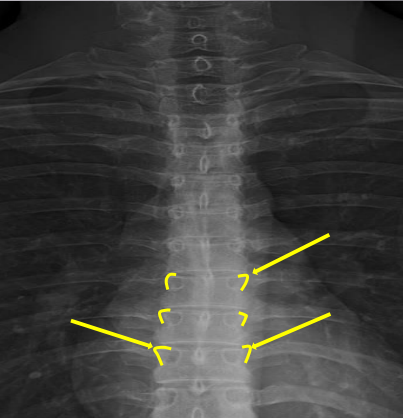

Femur heads

Superior iliac crests

Lateral iliac crests

Ischial tuberosities

Obturator foramen

S2 tubercle

Pubic symphysis

Sacral groove

Lateral aspect of sacrum

Medial aspect of ilium